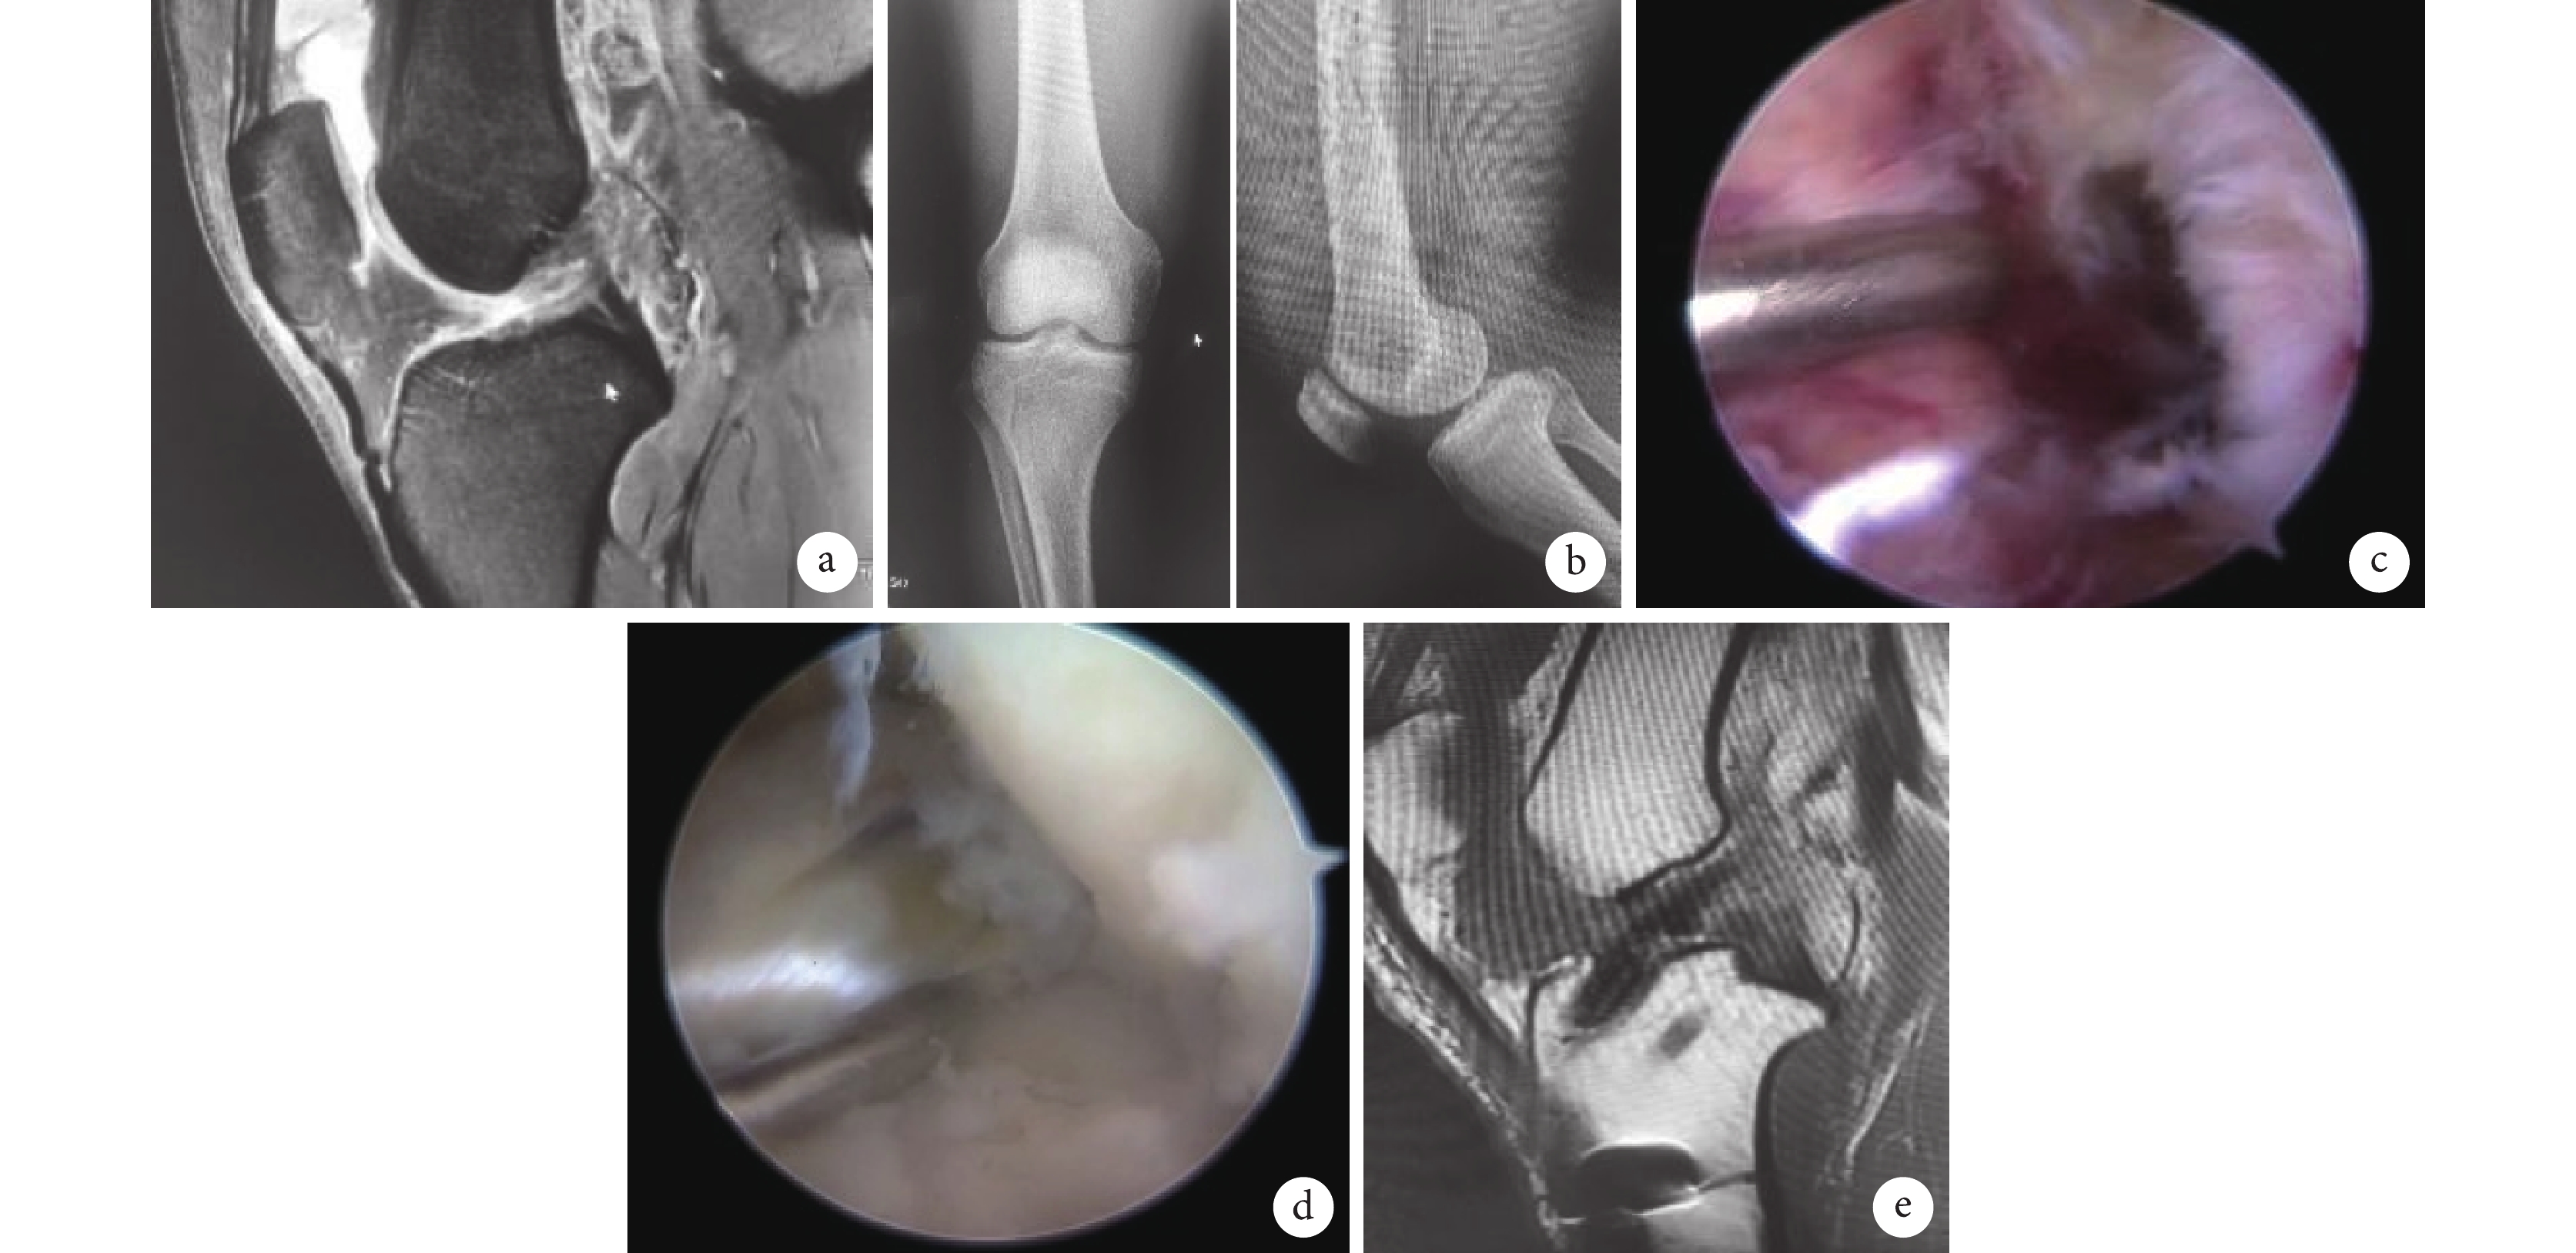

a. 術前MRI示ACL信號混雜不清;b. 術前正側位X線片;c、d. 術中關節鏡下探查示ACL斷裂;e. 術后12個月MRI示ACL恢復良好

Figure3. A 22-year-old male patient in the study group suffered ACL rupture of the right knee after sprained by playing footballa. Preoperative MRI showed mixed signals of ACL; b. Preoperative anteroposterior and lateral X-ray films; c, d. Intraoperative view under arthroscopy showed ACL rupture; e. MRI at 12 months after operation showed that the ACL recovered well